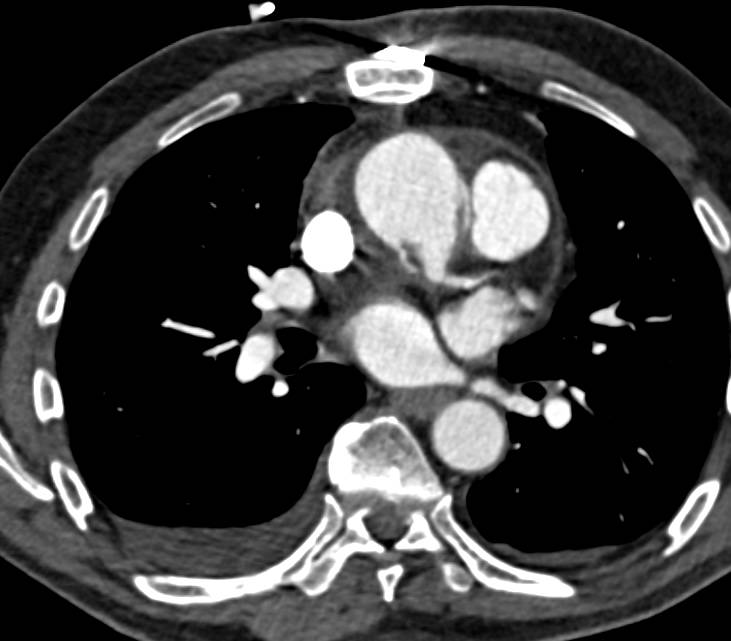

Infiltrating Carcinoma Left Breast with Axillary Adenopathy